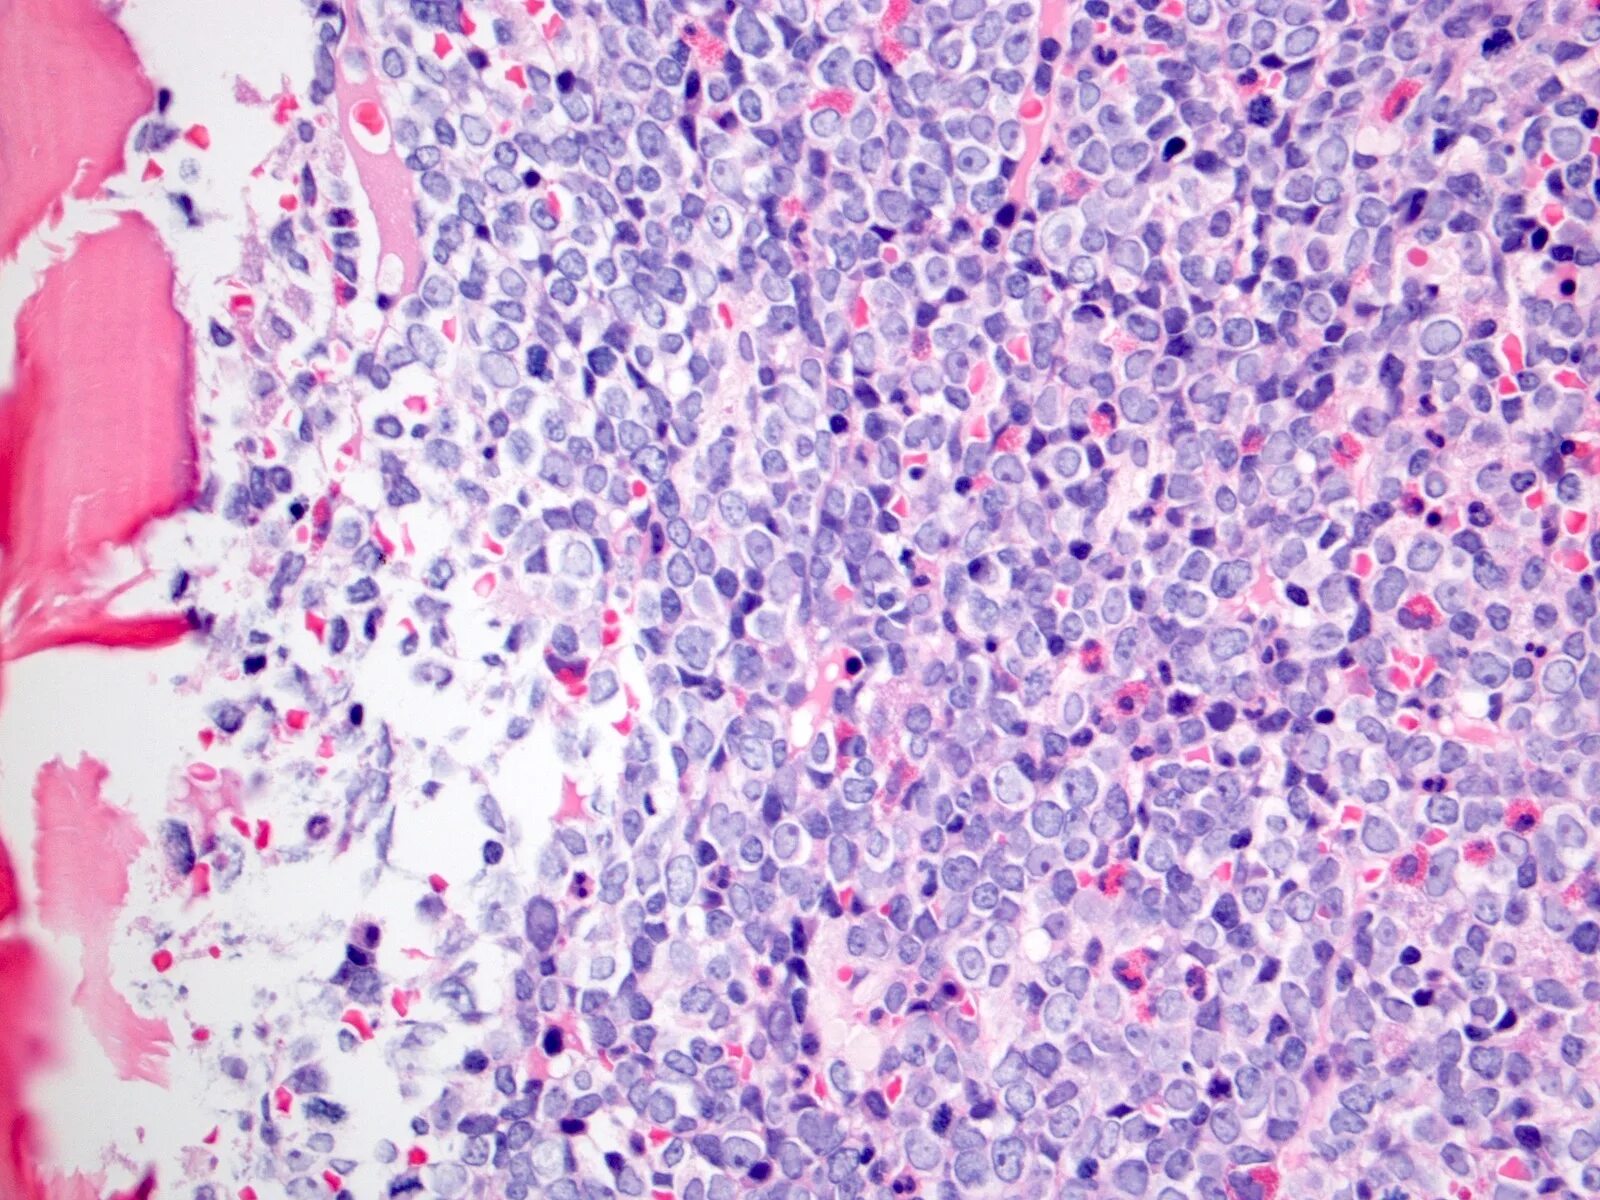

Лимфомы тесты